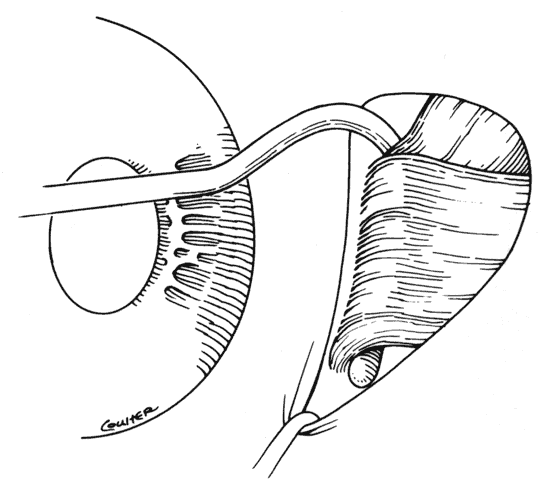

When approaching the superior and lateral rectus muscles that have had previous surgery, care should be taken to identify the superior oblique tendon and the inferior oblique muscles respectively. One should carefully free up attachments of these structures to the rectus muscle so that a normal anatomic relationship between the rectus and oblique muscles can be re-established. Frequently, the lateral rectus muscle will have adhesions to the orbital surface of the inferior oblique muscle as it passes underneath the lateral rectus. There is a propensity for the inferior oblique muscle to be drawn up into the insertion during resection procedures.37 When this occurs, the inferior oblique and lateral rectus muscle must be separated, and the inferior oblique muscle should be repositioned into its normal anatomic position (Figs. 30 through 33).

Fig. 31. The inferior oblique muscle has been incorporated into the insertion of the right lateral rectus.

Fig. 32. Sharp and blunt dissection is used to “free up” the inferior oblique muscle from the scleral side of the lateral rectus.